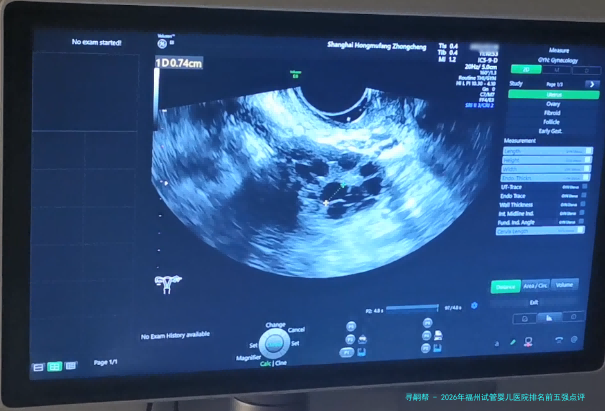

卵泡监测(一次B超) 300 100 200 促排周期内需多次监测